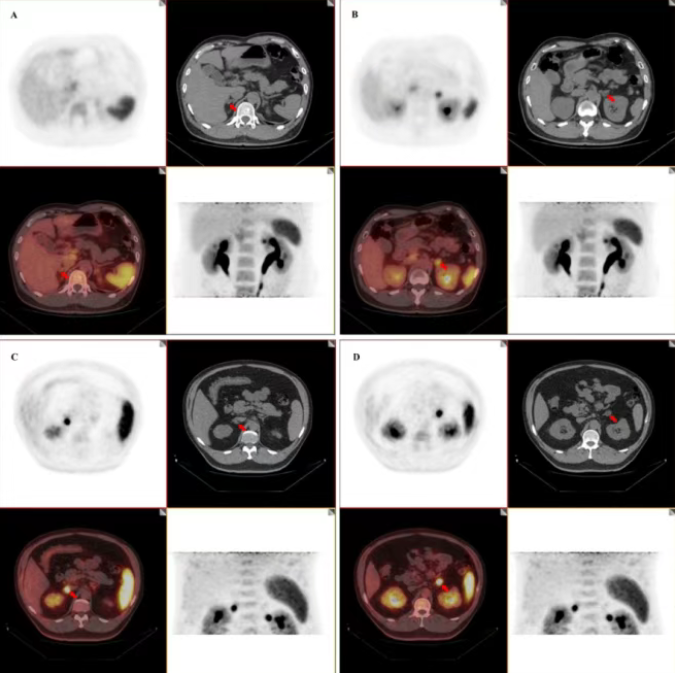

原发性醛固酮增多症(PA)是导致继发性高血压的主要原因,其治疗关键在于准确判断病变是单侧腺瘤还是双侧增生。长期以来,肾上腺静脉采血(AVS)是该分型诊断的金标准,但其操作复杂且有创。68Ga-pentixafor是一种新型PET示踪剂,它通过特异性结合病变组织中高表达的CXCR4受体,使病灶在核医学影像上清晰显影。

在这项前瞻性研究中,共197例PA患者被分为两组。PET组(137例)依据68Ga-pentixafor PET/CT结果决定手术方案:单侧显影则行同侧手术,双侧显影则在标准摄取值(SUVmax)更高的一侧手术。AVS组(60例)则依据传统AVS结果手术。术后平均27个月的随访采用国际PASO标准进行评估。

结果显示,两组患者在术后临床完全缓解率(PET组51.5% vs. AVS组35.1%)和生化完全缓解率(PET组82.1% vs. AVS组75.4%)上均无统计学显著差异,总体获益率也相近(PET组95.5% vs. AVS组93.0%)。这表明基于核医学影像的手术指导取得了与金标准方法同等的治疗效果。研究进一步通过受试者工作特征曲线分析,确定了SUVmax的最佳诊断临界值为5.5,此时识别功能性病灶的灵敏度达82.8%,特异度达92.6%。

尤其对于诊断更为复杂的双侧病变患者,68Ga-pentixafor PET/CT展现了独特优势。在PET组53例双侧影像学异常的患者中,有34例被该显像精准判别为“一侧阳性”,这些患者术后获益率达到100%。这体现了核医学分子影像不仅能够定位病灶,还能无创地评估其相对功能活性,为个体化手术决策提供关键信息。